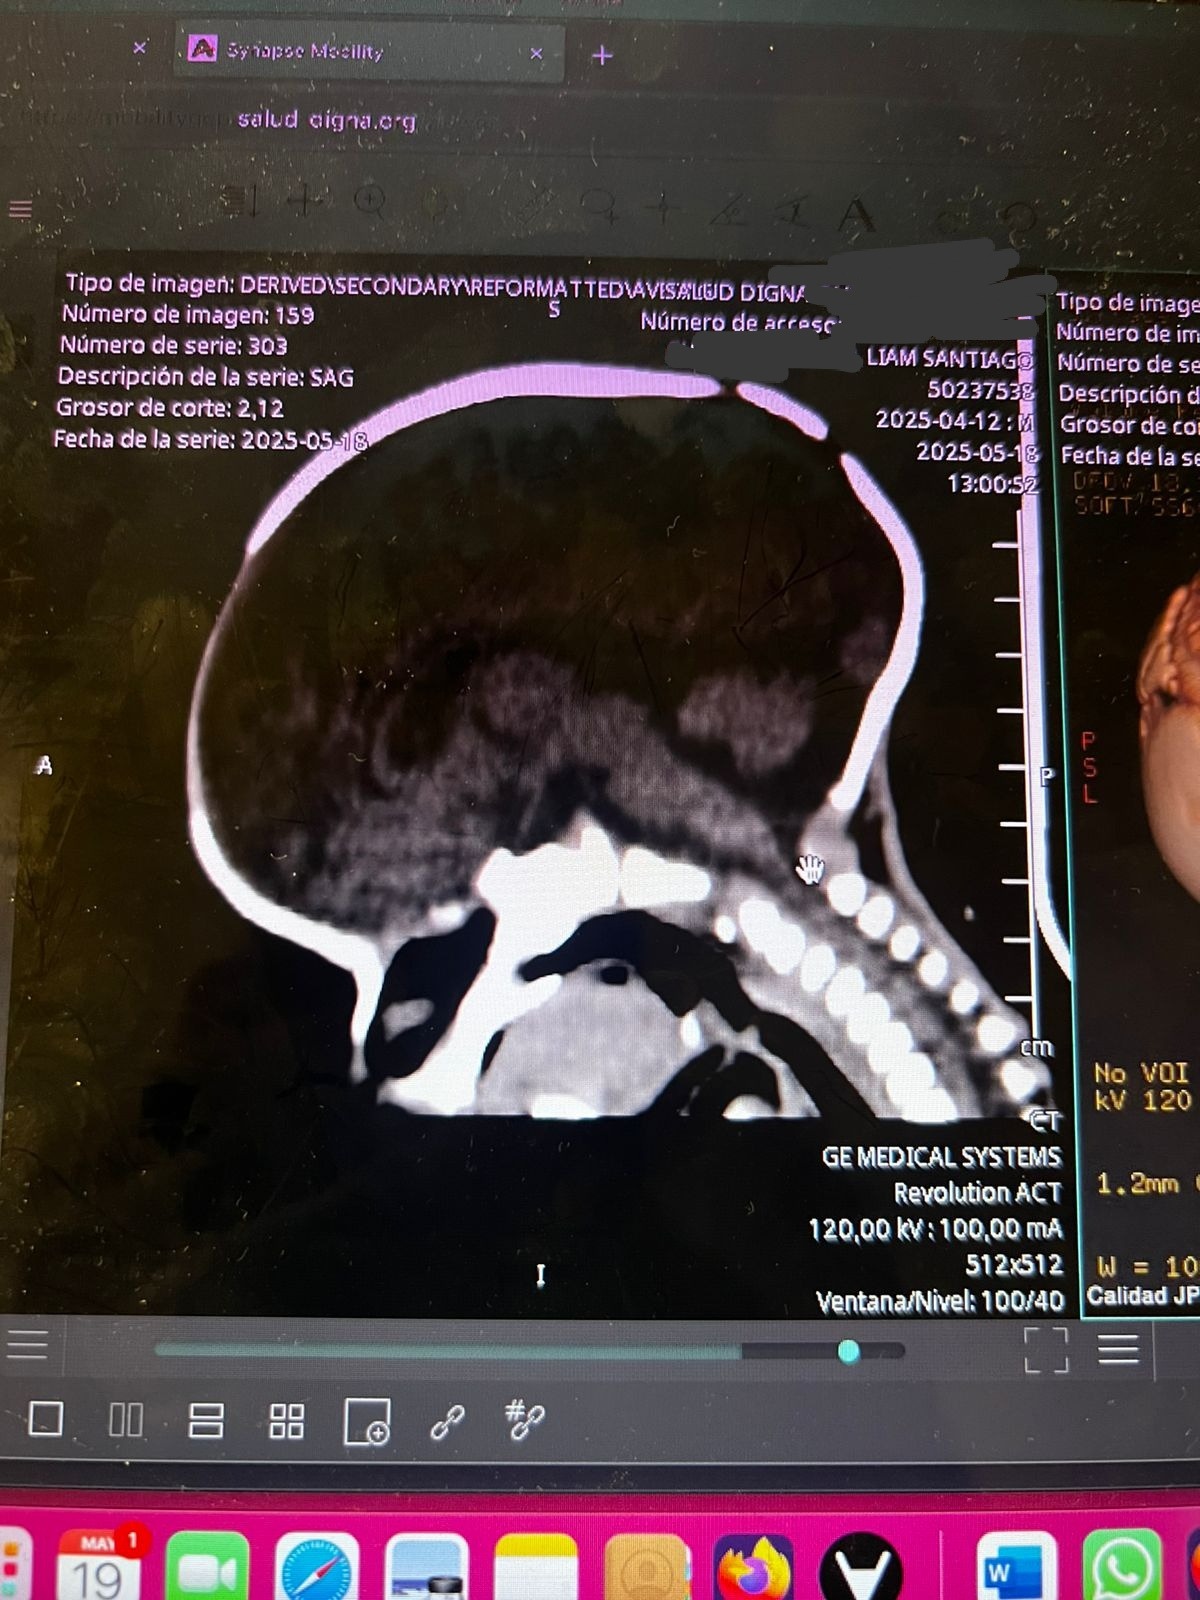

Hola mi nombre es Diana y hace aproximadamente un mes nació mi sobrino Santiago, ayer le acaban de detectar craneosinostosis y es necesario realizarle una cirugía en su cabecita lo más rápido posible para que su cerebro pueda tener un desarrollo adecuado, para realizar esta cirugía en los hospitales públicos hay lista de espera de seis meses aproximadamente y debido a la urgencia y que vamos contra reloj ya que se debe realizar en los primeros meses de vida que es cuando es menos riesgosa la operación por eso la única opción que nos queda es realizarla en un hospital privado por eso el costo tan elevado, les pido de todo corazón su ayuda cualquier aportación es de gran ayuda para poder juntar el dinero cuanto antes y el pequeño Santi pueda ser operado cuanto antes.